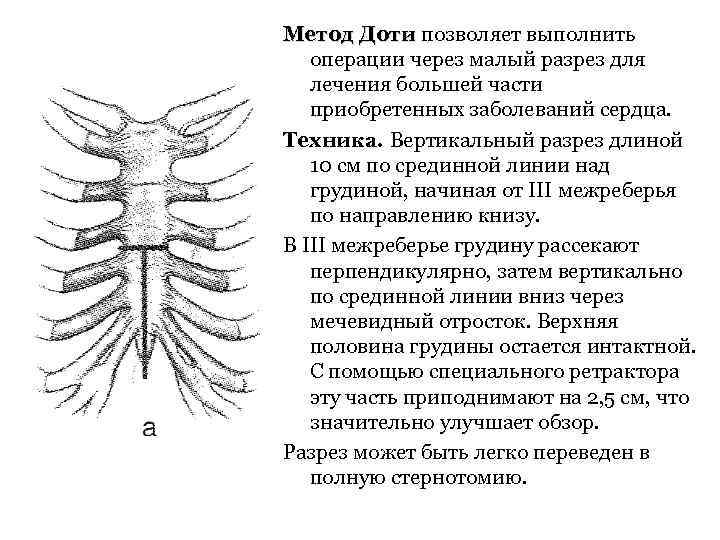

Метод Доти позволяет выполнить операции через малый разрез для лечения большей части приобретенных заболеваний сердца. Техника. Вертикальный разрез длиной 10 см по срединной линии над грудиной, начиная от III межреберья по направлению книзу. В III межреберье грудину рассекают перпендикулярно, затем вертикально по срединной линии вниз через мечевидный отросток. Верхняя половина грудины остается интактной. С помощью специального ретрактора эту часть приподнимают на 2, 5 см, что значительно улучшает обзор. Разрез может быть легко переведен в полную стернотомию.

Метод Доти позволяет выполнить операции через малый разрез для лечения большей части приобретенных заболеваний сердца. Техника. Вертикальный разрез длиной 10 см по срединной линии над грудиной, начиная от III межреберья по направлению книзу. В III межреберье грудину рассекают перпендикулярно, затем вертикально по срединной линии вниз через мечевидный отросток. Верхняя половина грудины остается интактной. С помощью специального ретрактора эту часть приподнимают на 2, 5 см, что значительно улучшает обзор. Разрез может быть легко переведен в полную стернотомию.